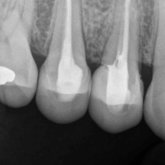

Porcelain crowns and restorations made in one appointment.

We make it a priority to incorporate the latest in dental technology in everything we do at our practice. ...